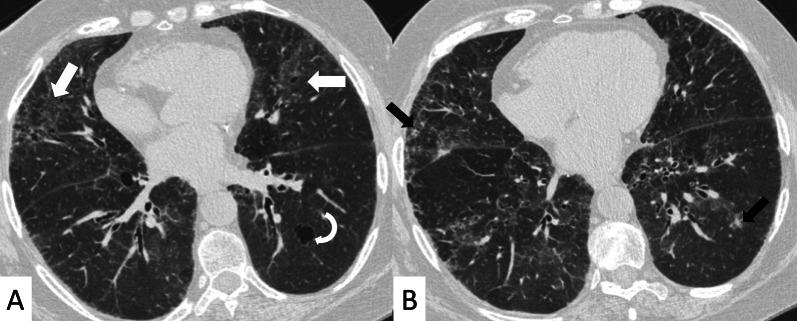

Connective tissue diseases (CTDs) include a spectrum of disorders that affect the connective tissue of the human body; they include autoimmune disorders characterized by immune-mediated chronic inflammation and the development of fibrosis. Lung involvement can be misdiagnosed, since pulmonary alterations preceded osteo-articular manifestations only in 20% of cases and they have no clear clinical findings in the early phases. All pulmonary structures may be interested: pulmonary interstitium, airways, pleura and respiratory muscles. Among these autoimmune disorders, rheumatoid arthritis (RA) is characterized by usual interstitial pneumonia (UIP), pulmonary nodules and airway disease with air-trapping, whereas non-specific interstitial pneumonia (NSIP), pulmonary hypertension and esophageal dilatation are frequently revealed in systemic sclerosis (SSc). NSIP and organizing pneumonia (OP) may be found in patients having polymyositis (PM) and dermatomyositis (DM); in some cases, perilobular consolidations and reverse halo-sign areas may be observed. Systemic lupus erythematosus (SLE) is characterized by serositis, acute lupus pneumonitis and alveolar hemorrhage. In the Sjögren syndrome (SS), the most frequent pattern encountered on HRCT images is represented by NSIP; UIP and lymphocytic interstitial pneumonia (LIP) are reported with a lower frequency. Finally, fibrotic NSIP may be the interstitial disease observed in patients having mixed connective tissue diseases (MCTD). This pictorial review therefore aims to provide clinical features and imaging findings associated with autoimmune CTDs, in order to help radiologists, pneumologists and rheumatologists in their diagnoses and management.

结缔组织病(CTDs)包括一系列影响人体结缔组织的疾病;它们包括以免疫介导的慢性炎症和纤维化发展为特征的自身免疫性疾病。肺部受累可能会被误诊,因为肺部改变仅在20%的病例中先于骨关节炎表现出现,且在早期阶段没有明确的临床发现。所有肺部结构都可能受累:肺间质、气道、胸膜和呼吸肌。在这些自身免疫性疾病中,类风湿关节炎(RA)的特征是普通型间质性肺炎(UIP)、肺结节和伴有空气潴留的气道疾病,而系统性硬化症(SSc)常表现为非特异性间质性肺炎(NSIP)、肺动脉高压和食管扩张。NSIP和机化性肺炎(OP)可见于多发性肌炎(PM)和皮肌炎(DM)患者;在某些情况下,可观察到小叶周围实变和反晕征区域。系统性红斑狼疮(SLE)的特征是浆膜炎、急性狼疮性肺炎和肺泡出血。在干燥综合征(SS)中,HRCT图像上最常见的表现是NSIP;UIP和淋巴细胞间质性肺炎(LIP)的报道频率较低。最后,纤维化NSIP可能是混合性结缔组织病(MCTD)患者中观察到的间质性疾病。因此,本图像综述旨在提供与自身免疫性CTDs相关的临床特征和影像学表现,以帮助放射科医生、呼吸科医生和风湿病科医生进行诊断和管理。